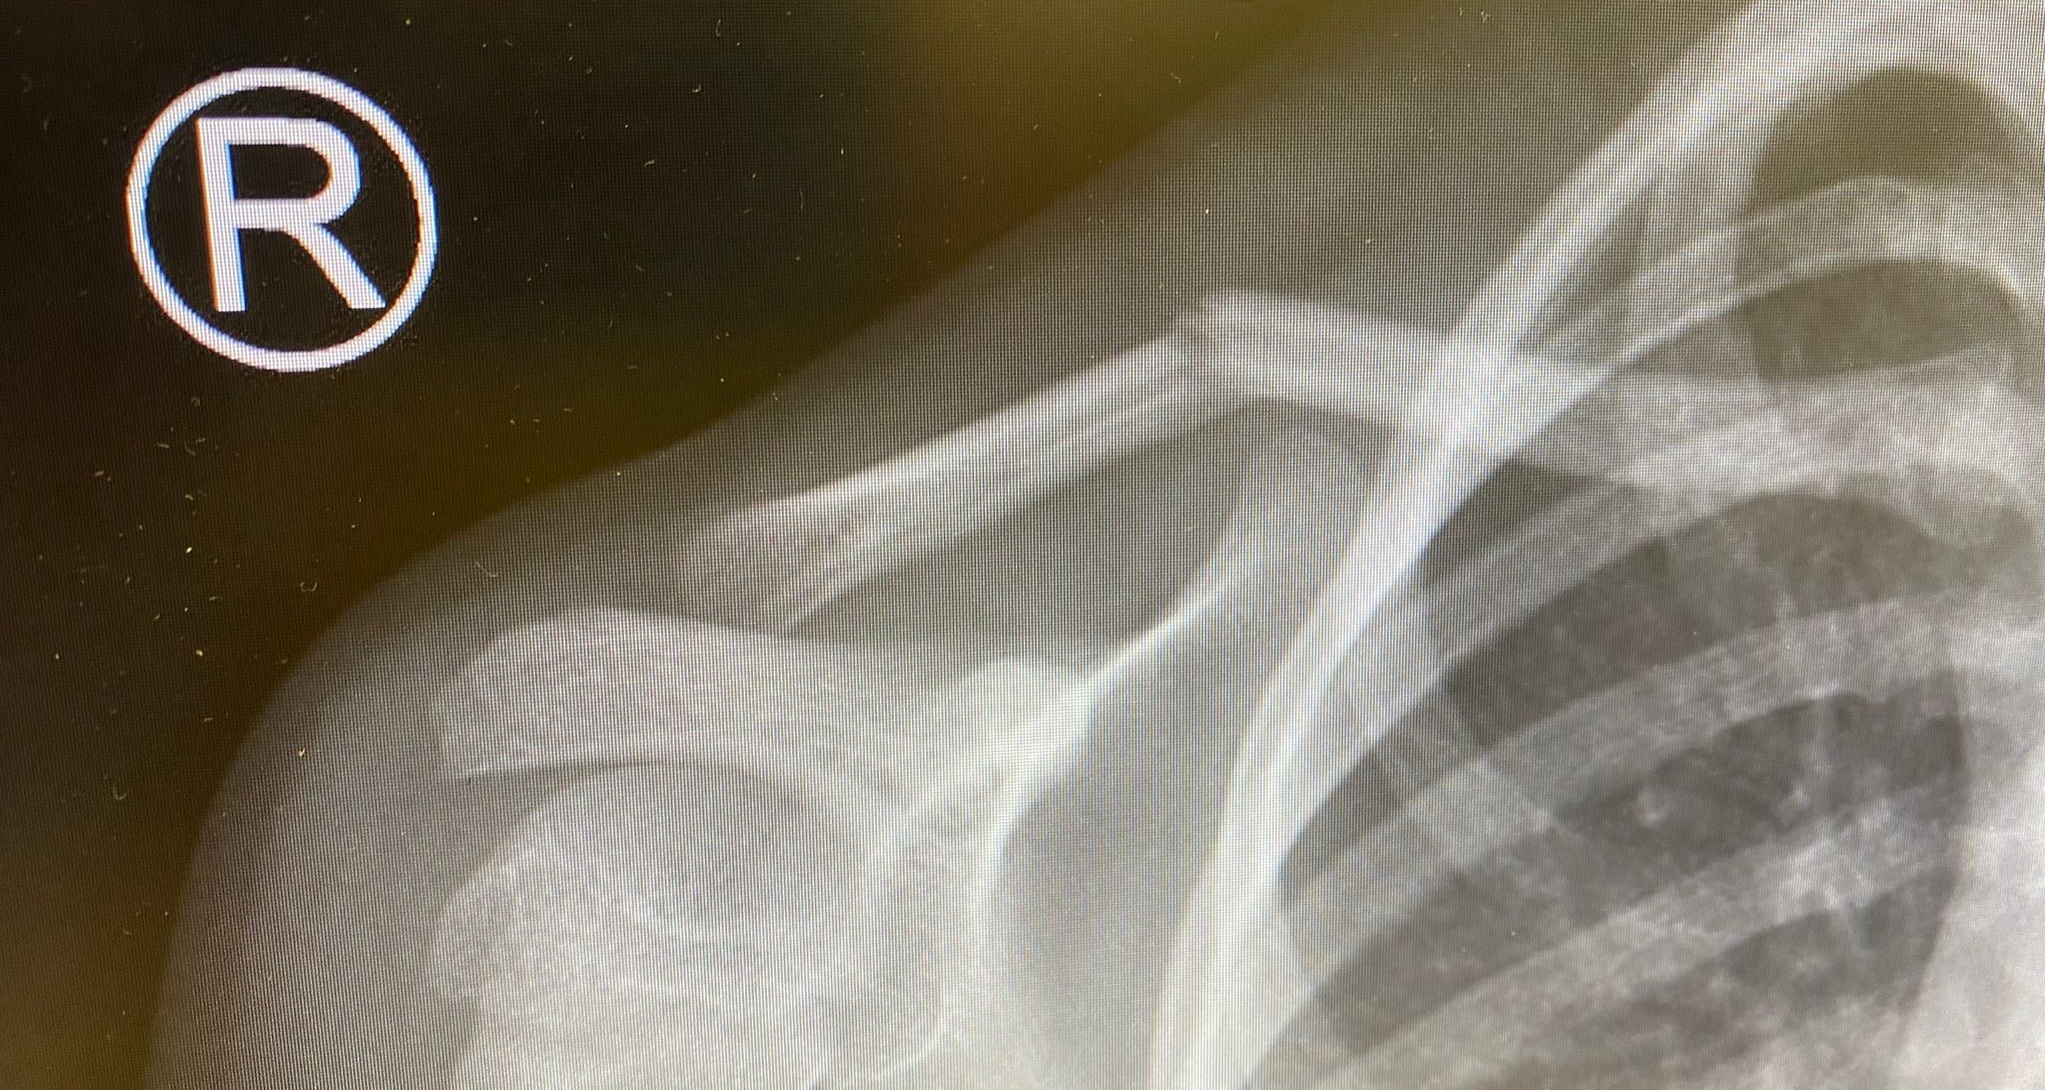

Deze module leert de beginnend beroepsbeoefenaar radiologisch diagnostisch laagcomplex onderzoek uit te voeren die een lage stralingsbelasting met zich meebrengen. Met als doel dat de beginnend beroepsbeoefenaar veilig en bekwaam kan assisteren bij laagcomplexe radiodiagnostische onderzoeken. De beginnend beroepsbeoefenaar kan een aantal

onderzoeken zelfstandig, maar onder supervisie van een radiodiagnostisch laborant of radioloog uitvoeren.